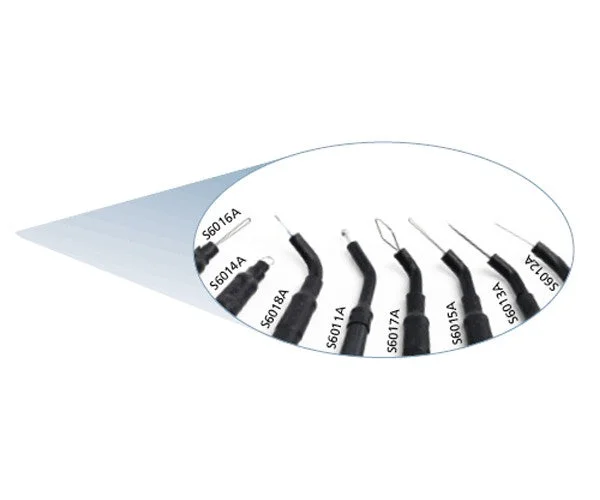

PERFECT S6014A round loop electrode 2 pcs

Straight round loop electrode